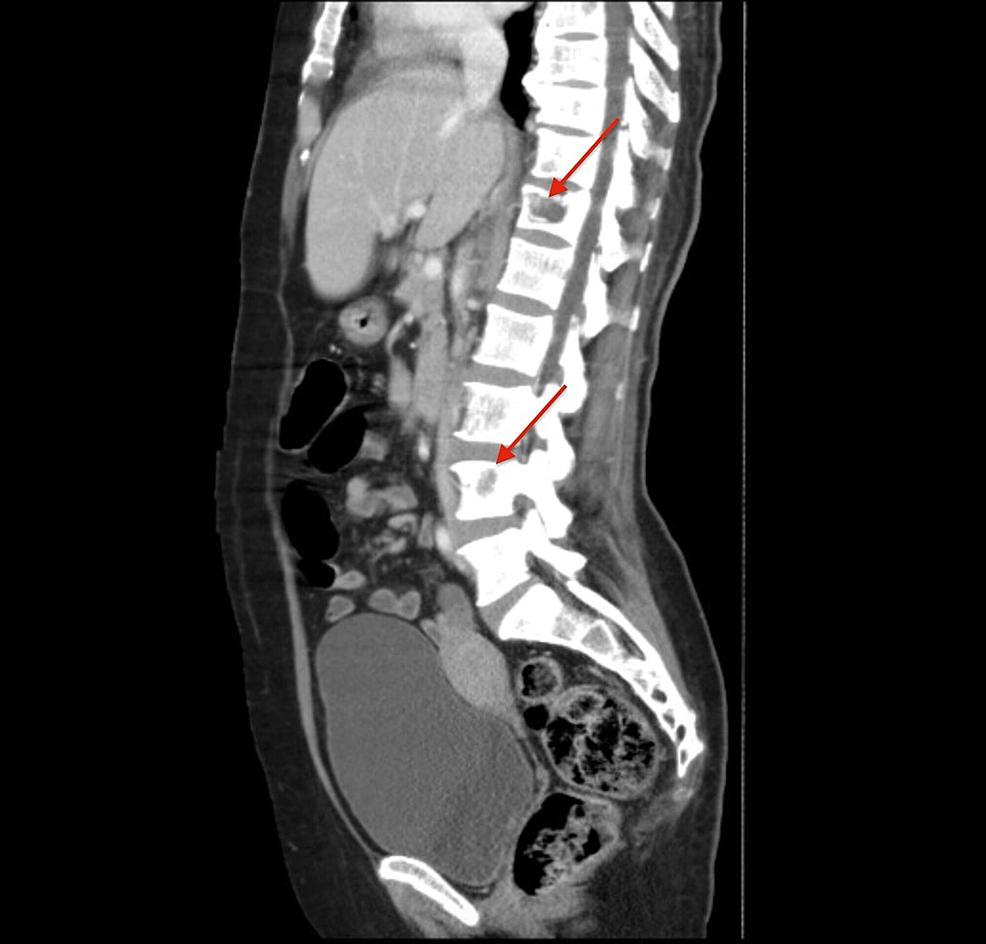

ct scan lumbar spine lytic lesions thoracic sagittal figure pulmonary pheochromocytoma widespread bony metastases malignant multiple section showing red cureus

Cureus | Malignant Pheochromocytoma With Widespread Bony And Pulmonary Metastases